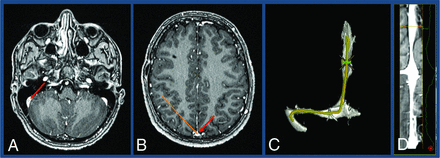

Straight-vessel views and 3D reconstructions of both TOF and contrast-enhanced images were created and reviewed to better characterize venous sinus anatomy and stenosis, as shown in Fig 2. The straightened vessel view was achieved using 2-click automatic vessel analysis (Vessel ASSIST; GE Healthcare). After the user selected the start and end points in the sigmoid sinus and superior sagittal sinus, the software automatically tracked the vessel and computed its centerline. The resulting vessel segmentation could be displayed as a 3D volume-rendered model or a lumen view (D). The lumen view is obtained by transforming the 3D vessel centerline into a straight line and displaying the corresponding perpendicular plane for each point on the line. For each position, minimum, mean, and maximum diameters were automatically computed.

A, 2-Click automatic vessel analysis start point selection in the sigmoid sinus (short arrow). B, 2-Click automatic vessel analysis end point selection (short arrow) in the superior sagittal sinus (long arrow). C, 3D volume-rendered vessel segmentation. D, Lumen view shows the straightened vessel segmentation.